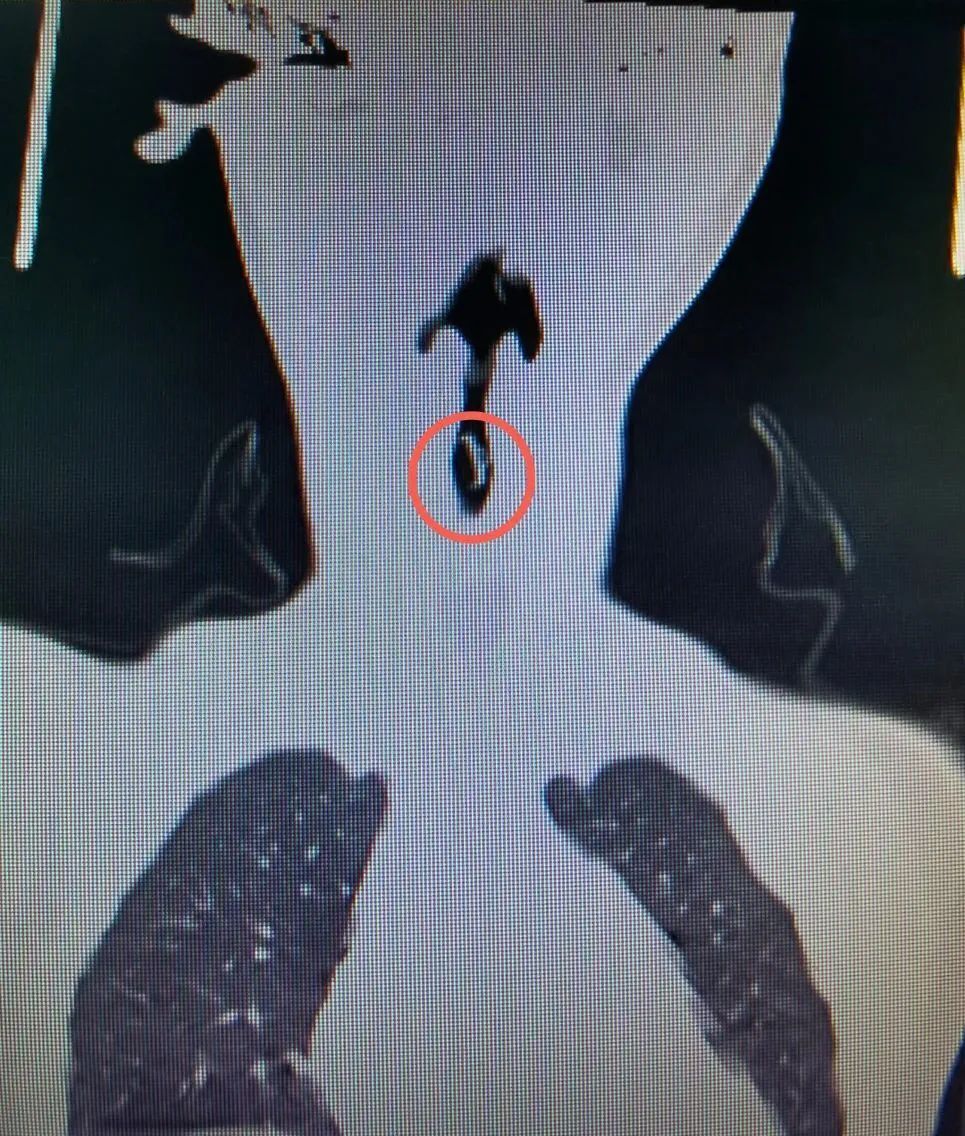

▲ 异物卡在气管内(正、侧位片)

眼耳鼻喉科值班医师黄江舟予行颈部CT检查,结果显示为气管内异物,异物长1.5cm,宽1.0cm,质地坚硬,且卡在气管内平对颈前第6、7椎体水平。只见男童口唇紫绀,呼吸急促、费力,频繁刺激性咳嗽,活动后加重,吸气三凹征,咽部明显充血。眼耳鼻喉科副主任甘世勇考虑到患儿情况危急,需要多科室进行联合救治,遂立即汇报医院当日的行政值班领导韦科越院长,韦院长指示:即刻启动多学科会诊方案,尽快对患儿进行抢救,取出气管内异物,确保患儿安全。

▲?取出的异物